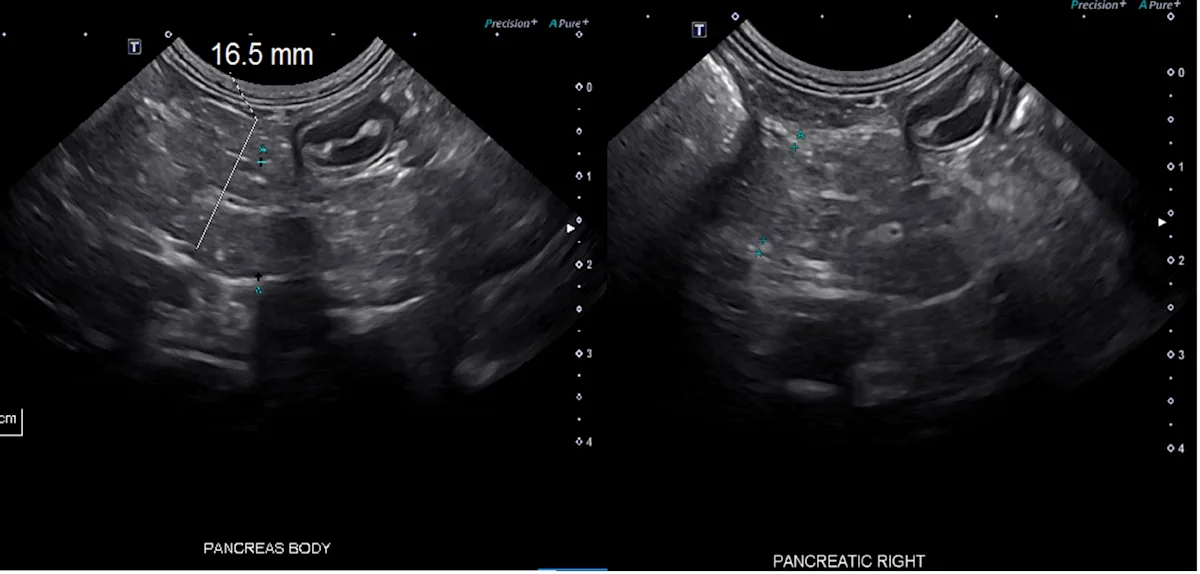

Ultrasonographic features vary but may include a normal to hyper- or hypoechoic pancreatic parenchyma. A heterogeneous appearance has also been suggested (Figure 1). Mass-like lesions may be noted and should not be assumed to indicate neoplasia, particularly in English cocker spaniels; in a study, ≈10% of English cocker spaniels with chronic pancreatitis had mass-like lesions.6,10

FIGURE 1 Ultrasound images of a 12-year-old, spayed crossbreed dog showing mild enlargement (1.65 cm) of the pancreatic body, with a heterogeneous echogenicity and irregular but well-defined pancreatic borders. Clinical history and a persistent mild increase in serum pancreatic lipase concentration, without other explanation, were consistent with diagnosis of chronic pancreatitis. Acute-on-chronic disease could also have been possible.